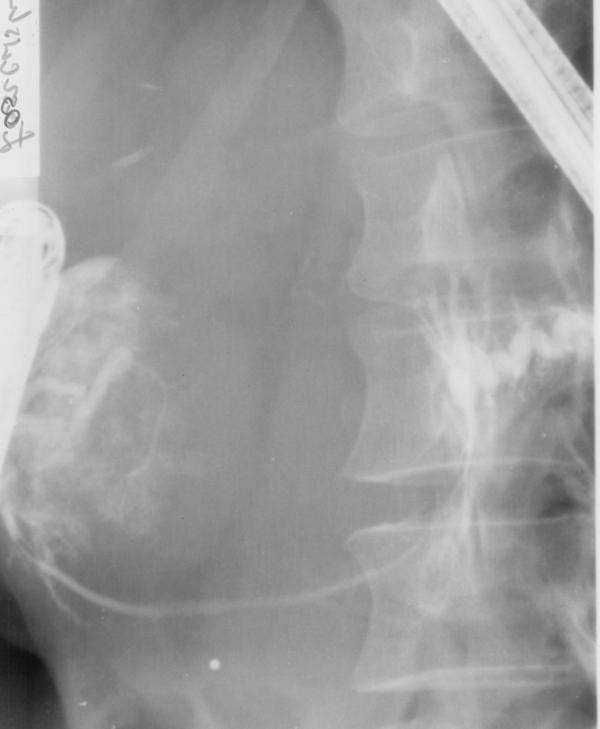

Patient underwent an abdominal ultrasound and computed tomography (CT) that revealed normal-sized liver and spleen, both without any focal changes and a gall bladder devoid of shading stones with visible polyps. Between the left lobe of the liver, stomach and the body of the pancreas there was thin walled pancreatic cyst with a diameter of 8 cm and a density of 9 HU (Figure 1). The pancreas was narrow with conspicuous Wirsung's duct within the body and the tail. The size of the head was normal. There were no enlarged lymph nodes. In organs of the small pelvis one couldn't see any changes in spite of a small amount of liquid. Thereafter, patient was transferred to Department of Gastroenterology. Endoscopic retrograde cholangiopancreatography (ERCP) examination revealed no communication between the cyst and the pancreatic duct (Figure 2). It also showed impression on the antrum of the stomach and the swollen papilla of Vater. In the head of the pancreas the main pancreatic duct was unchanged, from the neck to the body of the pancreas it was pressed and displaced by a tuberous structure (the wall of the duct was smooth with no secondary branches), in the tail the duct was extended and intricate. Pancreatic sphincterotomy was performed and only the tray was introduced to the tail. As the conclusion, endoscopist suggested pancreatic cystadenoma. Three days after ERCP patient presented fever, right-sided abdominal pain and redness in the region of the right kidney with positive Goldflam's sign. Next abdominal ultrasonography and CT revealed right pararenal inflammation with suggestion of abscess formation. The reason of inflammation remained unclear, but the probable relation to ERCP examination is conceivable. In March 2004 patient underwent successful incision and drainage of the abscess located around the right kidney. Urine culture revealed negative results. Patient was treated with ciprofloxacin and methronidazole.

After control CT that confirmed right pararenal abscess, complete healing Child's subtotal pancreatectomy and cholecystectomy were performed by open way. In the neck of the pancreas polycyclic, encapsulated, not connate to the environment formation was found (Figure 3). On account of the solid concrescence of the cyst and the portal vein, during the preparation over the vessel, lesion of its front wall (width: 0.5 cm) took place. The defect was sutured with leaving the fragment of the cyst wall on the portal vein (Figure 4). There were no macroscopic indications to qualify cyst as malignant. Afterwards the remaining part of the cyst was prepared.